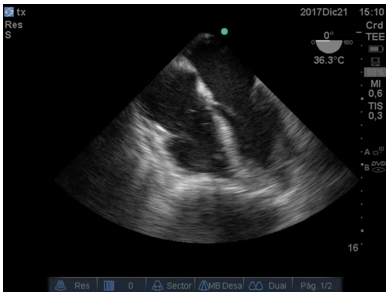

En la Figura 3:, se observa trombo cruzando por el foramen oval del tabique interauricular y trombosis en aurícula izquierda (AI).

Figura 3: Imagen de 4 cámaras donde se ve trombo en aurícula izquierda y otro pasando desde la aurícula derecha por el foramen oval. Cavidades derechas aumentadas de tamaño.

En la Figura 4:, se observa un trombo a nivel de la válvula mitral en condiciones de migrar hacia el ventrículo Izquierdo.